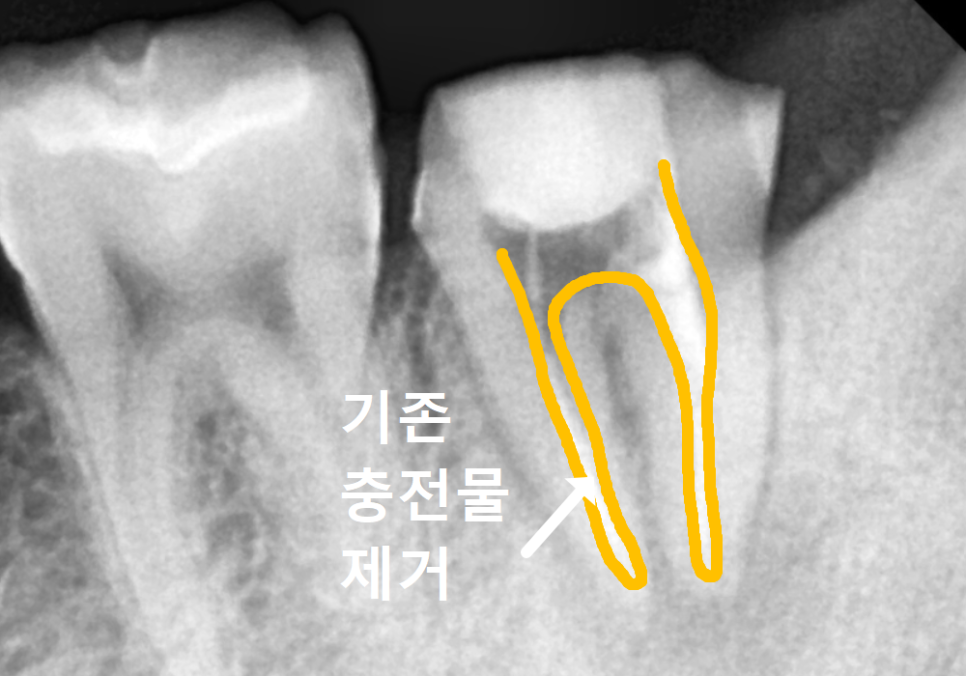

치료를 위해 보철물을 벗겨냈는데,,

예전 충치가 심했는지 남은 치아가 별로 없네요.

기존에 채워져 있던

오래된 충전물을 말끔히 제거한 뒤,

여러 차례 정밀한 소독 과정을 거쳤습니다.

이 과정에서 신경관 내부를

깨끗하게 살균함과 동시에,

녹아내린 뼈가 다시 차오르도록 유도하는

'칼시펙스'라는 약제를 사용해

꼼꼼히 처치해 드렸어요.

총 4번의 꼼꼼한 소독 과정을 거치며

한 달간 경과를 지켜보았습니다.